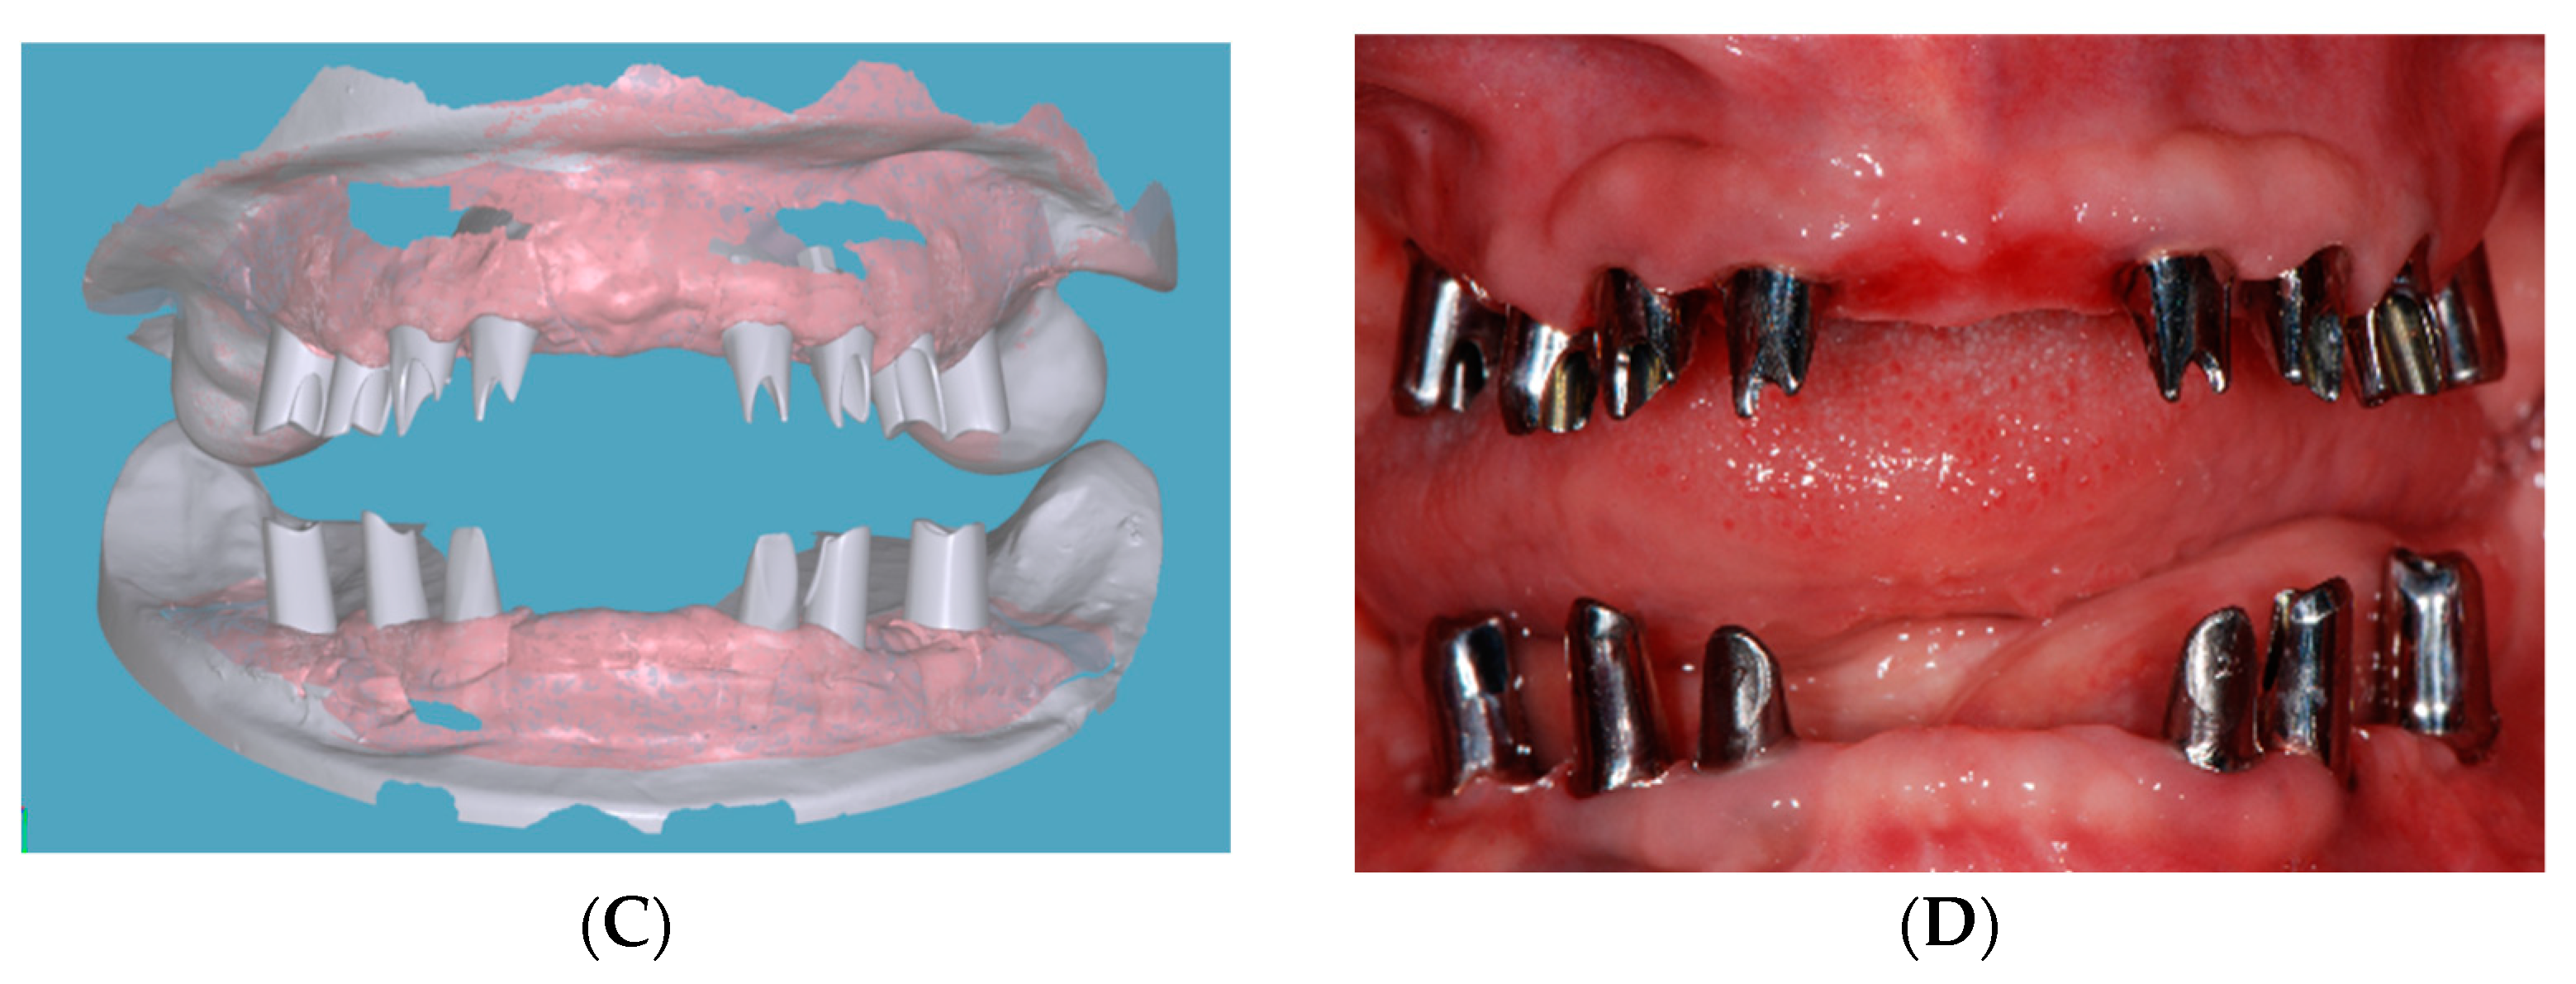

2.2. Foundational Phase: Elimination of Active Disease, Extraction and Fixed Provisional Prosthesis

2.4. Restorative Phase: Second Strategic Extraction and Conversion of Provisional Prostheses with Integrated Digital Workflow